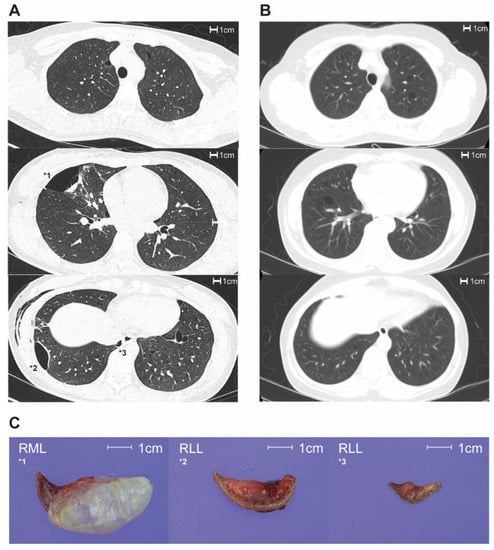

Figure 2 shows the ROC curves for BHD diagnosis. The AUC values for cyst number, maximal diameter, diversity of size, and diversity of morphology were 0.536 (95% CI, 0.346–0.726), 0.955 (95% CI, 0.873–1.000), 0.909 (95% CI, 0.790–1.000), and 0.727 (95% CI, 0.573–0.882), respectively. In the multivariate model combining cyst number, maximal diameter, and morphological diversity, the AUC value was best at 0.964 (0.887–1.000), which was not significantly different from the value observed for maximal diameter alone. The optimum cut-off value for maximal diameter was 2.1 cm, with a sensitivity of 99% and a specificity of 82%.

Figure 2. Receiver operating characteristic analysis for diagnosis of BHD. BHD: Birt–Hogg–Dube syndrome.